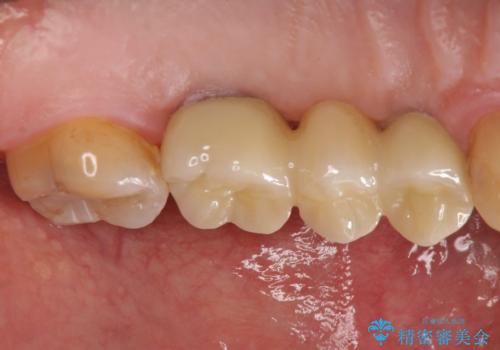

インプラント治療・セラミック治療を含む 全顎的虫歯治療

- 「 仕事が忙しく、虫歯を放置しすぎてしまった。この際全てきっちりと治したい。」と来院されました。

以上のような問題を、徹底的な虫歯治療、歯周外科、インプラント治療、部分矯正治療、精密根管治療を用いてひとつずつ解決ししっかりと長期的に食事を楽しめるような口腔内環境の再構築を目指します。